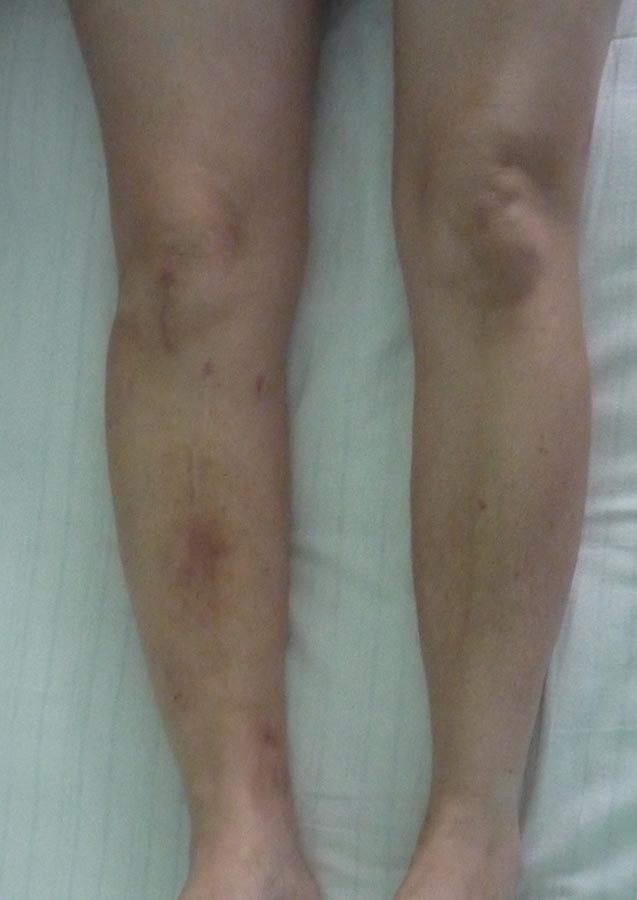

еще снимок. Эти снимки 01.07.2015 г.